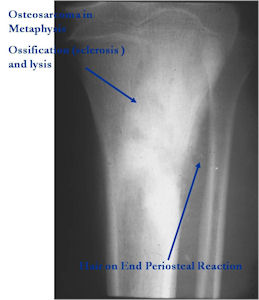

Aggressive Osteoblastoma vs. Osteosarcoma

Osteosarcoma:

- Cellular atypia

- High mitotic rate

- Atypical mitotic figures

- Abundant lacelike osteoid

- Permeative growth into adjacent bone and soft tissue

- Presence of neoplastic cartilage

- No peripheral shell of reactive bone

- Differentiation from osteosarcoma

- Osteoblastomas that are greater than 4 cm and that show prominent periosteal new bone formation may present problems in differentiation from osteosarcoma

- May have foci of lace-like osteoid, high cellularity and more than a few scattered mitotic figures but these characteristics usually occur independently in an osteoblastoma vs all these atypical characteristics being present in an osteosarcoma